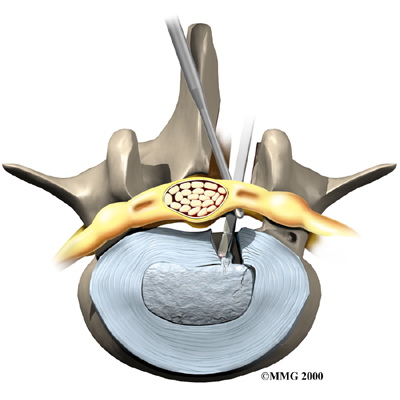

Microdiscectomy

Microdiscectomy is becoming the standard surgery for lumbar disc herniation. The procedure is used when a herniated disc is putting pressure on a nerve root. It involves carefully taking out part of the problem disc (discectomy). By performing the operation with a surgical microscope, the surgeon only needs to make a very small incision in the low back. Categorized as minimally invasive surgery, this surgery is thought to be less taxing on patients. Advocates also believe that this type of surgery is easier to perform, that it prevents scarring around the nerves and joints, and that it helps patients recover more quickly.

Related Document: FYZICAL Lexington's Guide to Lumbar Discectomy